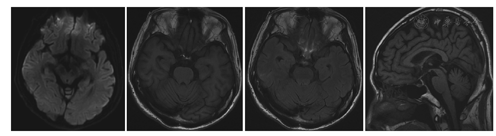

唑丙酸受体2-IgG、抗二肽氨基肽酶Ⅳ相关蛋白-IgG及抗IgLON5-IgG,德国欧蒙公司CBA法)提示血和脑脊液抗IgLON5-IgG抗体强阳性(图1);睡眠监测:发生呼吸事件48次,其中阻塞性暂停27次、中枢性暂停1次、混合性暂停20次、睡眠呼吸暂停低通气指数为7.4次/h(健康人小于5.0次/h),呼吸暂停平均时间51.9 s,最长时间98.9 s,整夜平均血氧98.1%,超过3%血氧下降事件39次,平均每小时下降6次,夜间最低血氧饱和度88%(健康人大于90%)。头颅MRI提示散在脱髓鞘病变及老年性改变,未见新发病变(图2)。结合患者血及脑脊液抗IgLON5抗体强阳性及相应的临床表现,考虑"抗IgLON5脑病"诊断成立,给予甲泼尼龙1 g×3 d、500 mg×3 d、250 mg×3 d、120 mg×3 d,然后改为52 mg甲泼尼龙片口服,1次/d,并予丙种球蛋白27.5 g静脉点滴×5 d。患者自用药后第2天复视症状即减轻,第3天患者睡眠中的喊叫及不自主运动即减轻,行走不稳也较前减轻。出院时体检:构音不清、双眼上视及外展、共济运动及步基均较前好转,口服甲泼尼龙片48 mg,1次/d和吗替麦考酚酯0.5 g,2次/d出院。2个月后随访,患者症状改善不再明显,停滞不前。